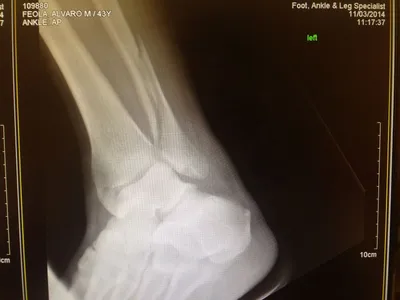

X-ray of Non Displaced Posterior Malleolar Fracture

Both the lateral and medial malleolus with fractures with the lateral malleolar fracture classified as a Weber B (at the level of the ankle joint) and the medial malleolar fracture almost transverse (Left x-ray). This is indicative of a Supination External Rotation (SER IV) injury. The fractures are repaired using open reduction with internal fixation (ORIF) technique and fixated with screws and a surgical fractue plate located at the fibular (Right x-ray).

A bimalleolar fracture is a fracture of the ankle that involves the lateral malleolus and the medial malleolus. Studies have shown that bimalleolar fractures are more common in women, people over 60 years of age, and patients with existing comorbidities. Surgical treatment will often be required, usually an Open Reduction Internal Fixation (ORIF). This involves the surgical reduction or realignment of the fracture followed by the implementation of hardware to aid in the healing of the fracture. Usually a plate and screws will be used on the fibular fracture and screws, screws and pins, pins or tension band will most commonly be used on the medial malleolus fracture. A bimalleolar "equivalent" fracture is a fracture of the fibula with rupture of the superficial and deep portion of the deltoid ligaments leaving the medial malleolus intact. Surgical management is common due to the instability of the fracture and displacement of the talus laterally.

The x-ray images below demonstrate another case of a bimalleolar ankle fracture in both and oblique view (left) and anterior - posterior view (right).